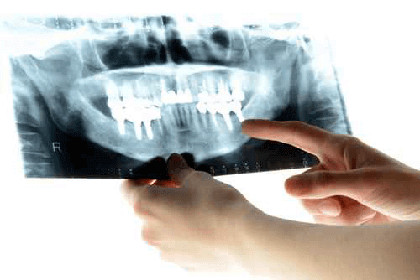

当院では3Dデジタル矯正でさらに多くのメリットをもたらしています。

一般的なようで実は技術力を必要とされる裏側矯正は3Dデジタル矯正でそのデメリットが解消されています。

3Dデジタル矯正が治療の効率化を実現

表側矯正よりも矯正歯科医の技術レベルを必要とされ、治療の段階も少し複雑なので治療期間は長期になりやすかった裏側矯正ですが、3Dデジタル矯正の導入により